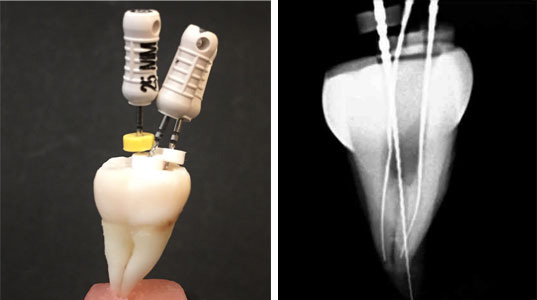

③神経の穴にテストファイルを挿入し、歯の根の先端を探り、長さを測ります。

④歯の根の長さに合わせて、神経の穴をたくさんの道具を使って、少しずつ確実に大きくしながら神経を取っていきます。